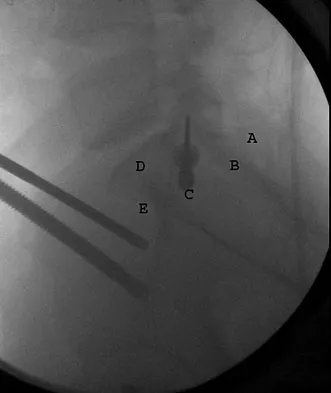

What letter in Figure 33 marks the correct starting point for a transiliac pelvic screw?

Explanation